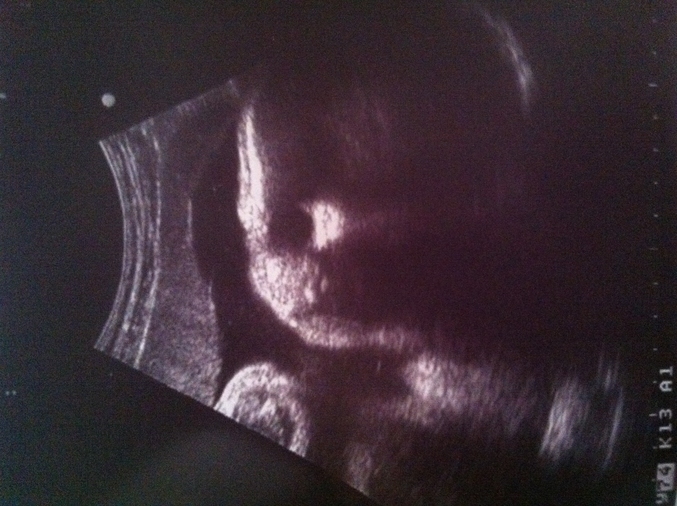

35 недель)) Вот и мы)

Наши будни, наши неделькинаши 35 и рассказ для памяти. Кому интересно, прошу..

Вот и состоялось наше очередное узи( не выдержала душа мамы и пошла платно на УЗИ) Бесплатное плановое мне назначили на 39 неделе беременности, а так как были проблемы с плацуентой, я не стала ждать)

Пункт 1 . Оказывается на прошлом УЗИ врач ошибся и назначили мне актовегин совсем зря, так как никакая у меня не маленькая плацента по пплощади, просто не увидели, даже допллер сделали и наш мася в полном порядке; ВЫВОД: ДЕВОЧКИ НЕ ВЕРЬТЕ СРАЗУ ВРАЧУ, А ЕСЛИ ЕСТЬ БЕСПОКОЙСТВА, ПЕРЕПРОВЕРЬТЕ СРАЗУ,ЧЕМ ТРАТИТЬ СВОИ НЕРВЫ И НАРУШАТЬ СПОКОЙСТВИЕ РЕБЕНКА...

Пункт 2.В свои 35 без 2 дней наш вес 2700, что сказали много для такого срока) Топтышь растет))

Немного мед. показателей простыми словами:

Голова-92мм

Длина бедренной кости-109мм

Длина костей голеня-60-60мм

Длина предплечевых костей- 61-61мм

Плацента- зрелость 2 степени.

Размер плода - соответствует 35 недели.

Тетя узист запретила есть булки и шоколад, тк ты уже по вполне доношены по размерам по из словам, а ПДР у нас 19.06.2013.